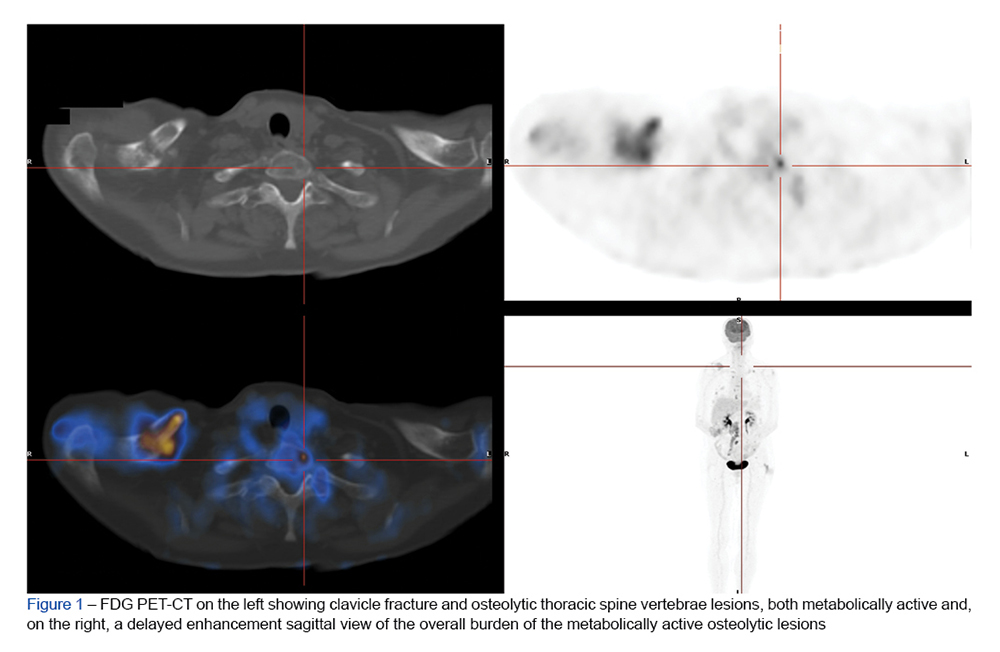

Non-secretory multiple myeloma is a rare form of the disease that presents a diagnostic challenge. A 69-year-old woman presented to the emergency department with a pat...